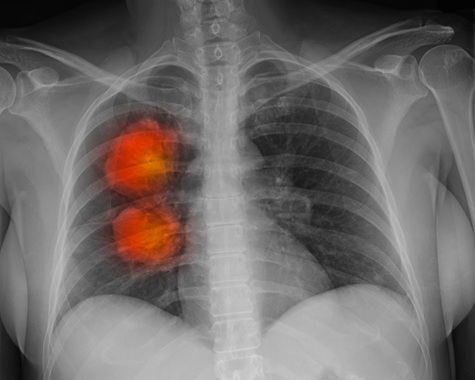

Más de 60 mil pacientes con cáncer en Inglaterra, no reciben la radioterapia necesaria

Londres, Inglaterra, Reino Unido, Europa.- Más de 60.000 pacientes con cáncer al año en Inglaterra no reciben la radioterapia que necesitan, y algunos se enfrentan a esperas de hasta seis meses para comenzar el tratamiento, según un estudio.

Expertos internacionales coinciden en que más de la mitad (53%) de los pacientes con cáncer suelen necesitar radioterapia, pero un análisis exclusivo de los últimos datos del NHS en Inglaterra muestra que solo el 35% la recibe. El estudio de la organización benéfica Radiotherapy UK reveló que 181.023 pacientes con cáncer deberían haber recibido radioterapia, pero solo 120.569 lo hicieron, lo que deja a 60.455 pacientes al año sin radioterapia.